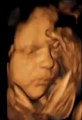

- Autora principal del estudio, Kimberley Whitehead Los investigadores agregan que el hipo está presente incluso en las primeras etapas de un embarazo. Según informes, el espasmo ocurre a menudo en la etapa del feto y puede comenzar tan pronto como a las nueve semanas.